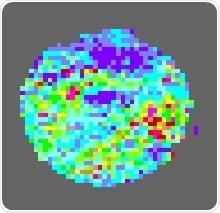

The image shows the blood flow in the surface blood vessels of a mouse that was given M-3.

The attached images were taken from laser scans of the skin of mice with diabetes. They show blood flow through the small blood vessels in the skin. The blue colors signify low blood flow. Red, yellow and green colors, represent higher blood flow.

Image one was from an animal that had not been given M-3, and indicates a problem with blood flow. Image two, was from a mouse that had received M-3, and it shows improved blood flow.